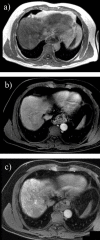

Hepatocellular carcinoma is a major health issue, ranked the fifth most common tumor and currently being responsible for a third of the cancer-related deaths globally, with an ever-increasing number of fatalities. Current advances in contrast-enhanced imaging techniques such as contrast-enhanced ultrasonography, multi-detector computed tomography and diffusion-weighted magnetic resonance imaging are improving the rate of hepatocellular carcinoma diagnosis. Contrast-enhanced ultrasonography has widely become the first choice in liver tumor assessment, as it is faster, simpler and safer than other forms of diagnostic imaging. On the other hand, cross sectional computed tomography is frequently employed when a hepatic formation is suspected of malignancy and allows a more accurate characterization of lesions through multiphasic multi-detector computed tomography technology. Diffusion weighted magnetic resonance imaging represents another addition to the wide range of diagnostic and prognostic techniques available for patients with hepatocellular carcinoma and is currently regarded as one of the best tools for the characterization of these lesions. Furthermore, groundbreaking biomarkers for hepatocellular carcinoma are being discovered, although alpha-fetoprotein remains one of the most frequently used serum test in the early stages. Nonetheless, further advances are required for the detection of small liver carcinomas.